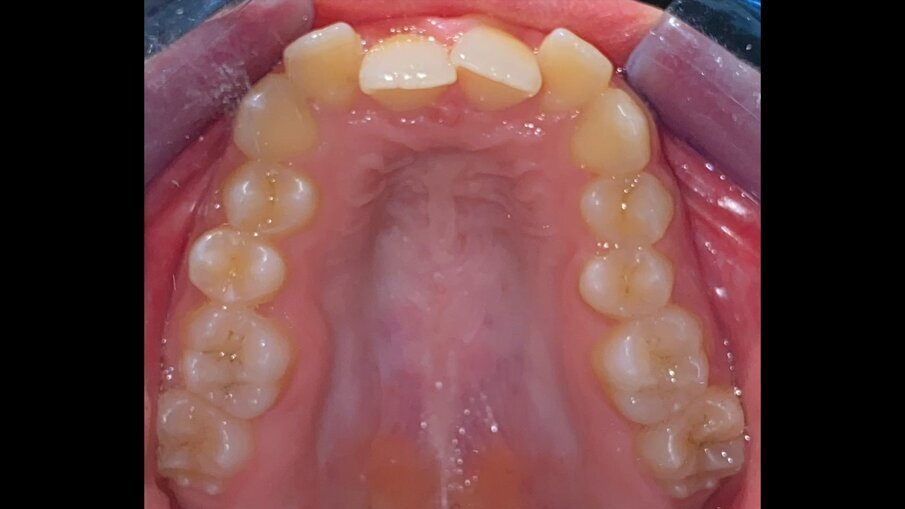

All’esame obiettivo intraorale si riscontra sul piano frontale un severo morso profondo con precontatto traumatico degli incisivi superiori contro la papilla retroincisiva e le rughe palatine anteriori durante la massima intercuspidazione, con overbite di 10 mm (Fig. 5). Dalle foto laterali si evidenzia una malocclusione di Classe II divisione 2 con scissor bite dell’elemento 1.5 (Figg. 6, 7), mentre dalle foto occlusali si rileva un grave affollamento con contrazione di entrambe le arcate maggiore nella zona premolare (Figg. 8, 9). L’analisi di Bolton mostra un eccesso superiore 3-3 di 2,34 mm (73,6%) e 6-6 di 2,76 mm (88,8%). L’analisi cefalometrica evidenzia una Classe II scheletrica, modello facciale normodivergente, angolo interincisale aumentato, incisivi superiori e inferiori retroinclinati (Fig. 10). La radiografia panoramica mostra la presenza dei germi dei terzi molari, assenza di parallelismo tra le radici dei premolari inferiori (Fig. 11) e una sovraeruzione degli incisivi inferiori che crea un doppio piano tra gli incisivi e i molari, segno di una curva di Spee molto profonda.

Fig. 8_Occlusale superiore pre-trattamento.